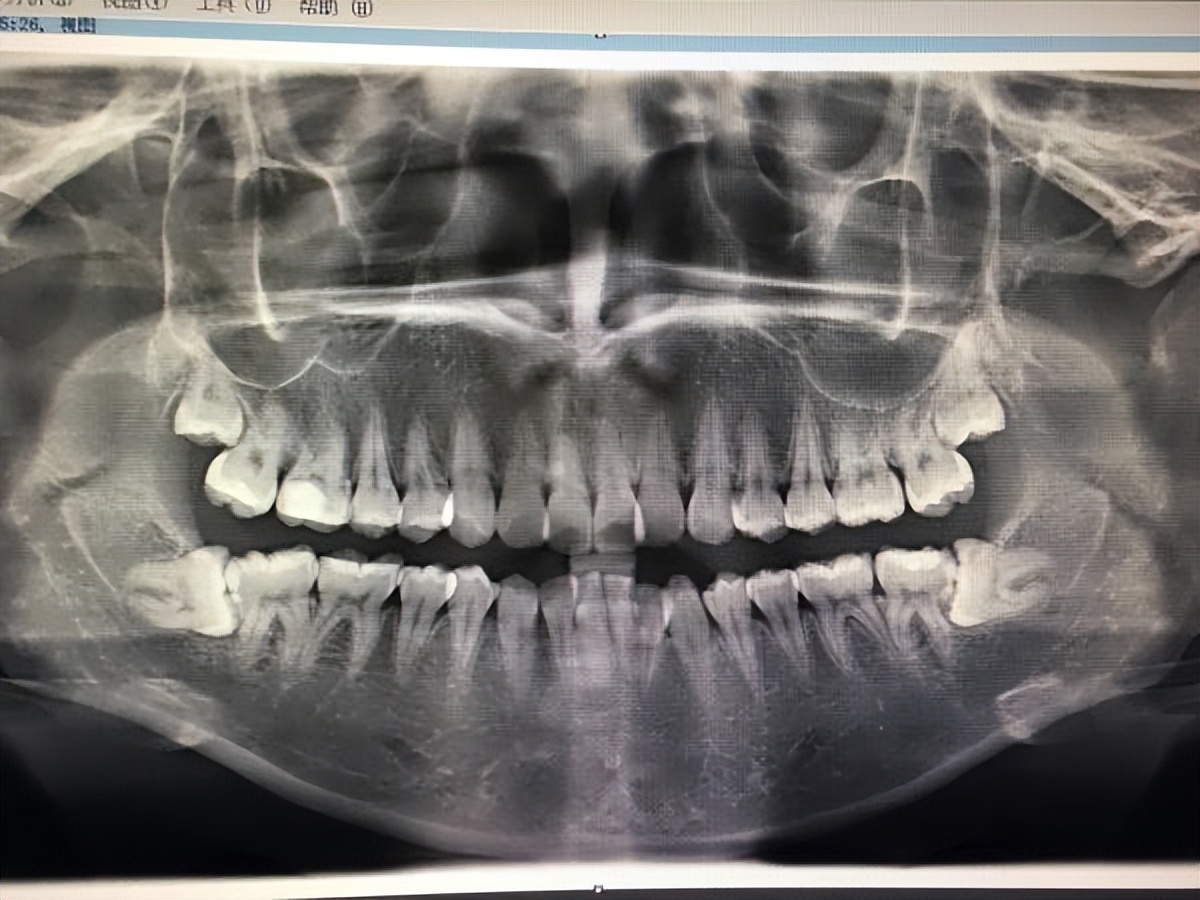

如果照镜子没发现自己有智齿?嘿嘿,那先别高兴太早。口内看不见不等于不存在,也有可能是智齿阻生了。这时候拍个牙片就能清晰看到有没有智齿,智齿长的位置怎么样,要不要拔,一切清晰明了。如果发现长智齿了也不要着急,让牙医来检查一下是不是可以正常萌出,有无龋坏,若没有问题,那么智齿也不一定非得拔除。